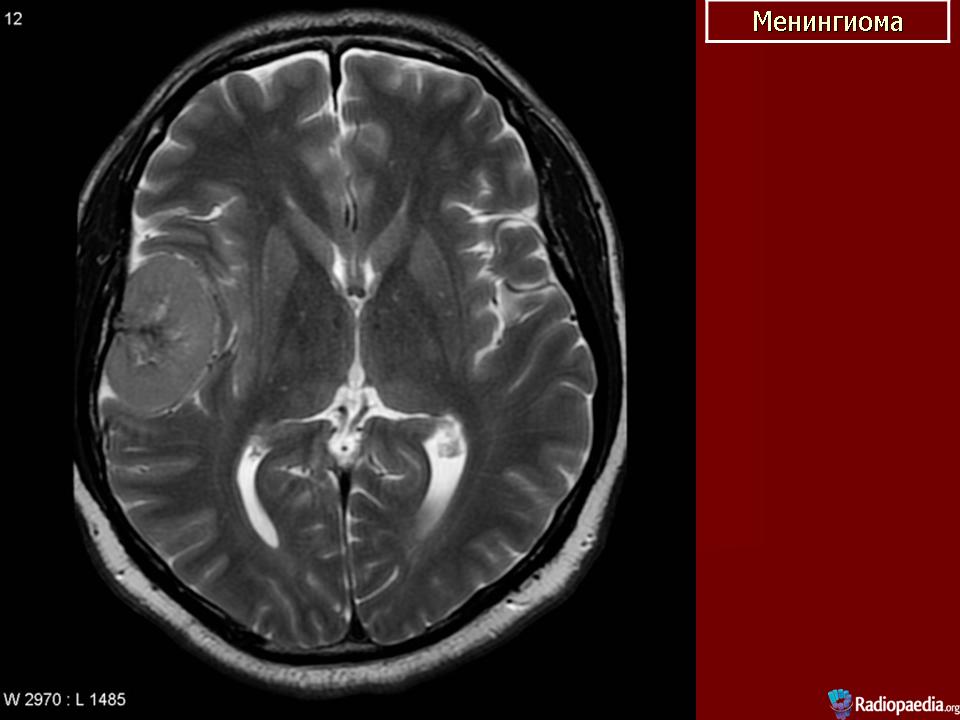

Менингиома.

Предложенный Харвеем Кушингом термин менингиомы относится к опухолям, произрастающим из твердой мозговой оболочки мозга. Менингиомы могут встречаться интракраниально или по ходу спинномозгового канала. Они произрастают из клеток Пахионовых грануляций, участвующих в резорбции ликвора.

Менингиомы обычно обнаруживаются на поверхности мозга, либо на его конвекситальной поверхности, либо на основании черепа. В редких случаях менингиомы встречаются в полости желудочков или внутрикостно. Проблема в классификации менингиом возникает из-за того, что клетки опухоли могут быть представлены клетками мезенхимы и клетками эпителия. Другие мезодермальные структуры также могут дать начало росту опухолей (например, гемангиоперицитомы или саркомы).